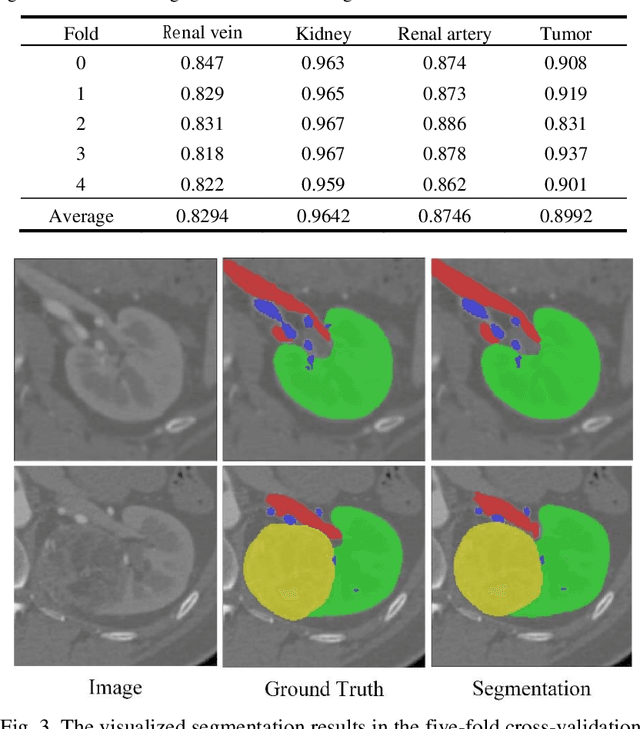

Accurate and automated segmentation of multi-structure (i.e., kidneys, renal tu-mors, arteries, and veins) from 3D CTA is one of the most important tasks for surgery-based renal cancer treatment (e.g., laparoscopic partial nephrectomy). This paper briefly presents the main technique details of the multi-structure seg-mentation method in MICCAI 2022 KIPA challenge. The main contribution of this paper is that we design the 3D UNet with the large context information cap-turing capability. Our method ranked eighth on the MICCAI 2022 KIPA chal-lenge open testing dataset with a mean position of 8.2. Our code and trained models are publicly available at https://github.com/fengjiejiejiejie/kipa22_nnunet.